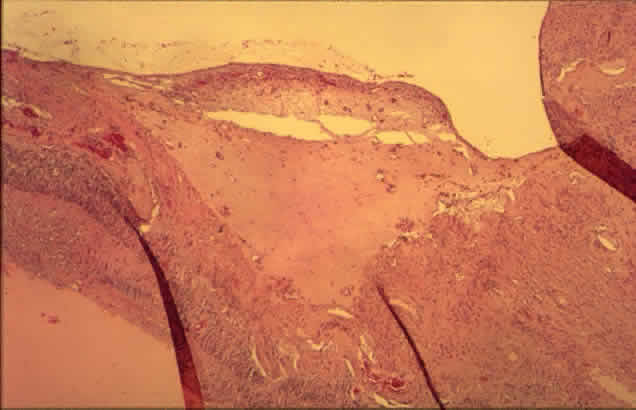

All of these changes are forerunners of proliferative retinopathy. Patients are unlikely to develop proliferative retinopathy before 10 years' duration of diabetes, but thereafter the incidence rises steadily.31,32 Rarely, proliferative retinopathy with vitreal hemorrhage can be the presenting sign in younger patients.48 As in other diseases associated with retinal neovascularization, the stimulus for new vessel formation in diabetes appears to be ischemia. The retina is uniquely dependent on oxygen: its demand on a unit-to-weight basis exceeds that of all other tissues, including the brain.7 A number of growth factors may act on the retina, including somatomedin C (insulin-like growth factor I), platelet-derived endothelial growth factor, fibroblast growth factors, angiogenin, and others.49 According to one recent study of samples of neovascular membranes obtained at vitrectomy from diabetic patients, only vascular endothelial growth factor was present in all specimens.50 This same factor is also present at significantly higher levels in the vitreous in eyes with proliferative retinopathy than in those without the disease.51 The precise role of the different factors in the promotion of neovascularization remains to be elucidated. New vessels that develop on or within a disc diameter of the optic nerve head are termed new vessels at the disc (NVD) (Color Fig. F). Those that develop anywhere else on the retina are called new vessels elsewhere (NVE). NVD indicate a diffuse retinal ischemia, whereas with NVE, the ischemia may be more localized, occurring at a site of previous arteriolar closure or capillary dropout. NVE can occur peripherally as well as in the posterior pole.52 Histologically, new vessels develop between the retinal surface and the posterior surface of the formed vitreous (Fig. 12). With NVE, there is a demonstrable break through the internal limiting membrane (Fig. 13).20 Early-developing new vessels have lumina even at the proliferating tips.53 Active new vessels have endothelial cells and pericytes, with fenestrations. Morphologically, fenestrations are areas ranging from 40 to 80 nm in diameter where the cell membranes are focally fused, and are normal findings in capillaries outside of the retina and brain. They allow increased permeability and are responsible for the diffuse leakage of fluorescein seen from new vessels on angiography. Inactive or “ghost” new vessels are acellular, having lost both endothelium and pericytes.39 With time, fibrous tissue develops and accompanies the new vessels. The vessels themselves may leak and bleed into the vitreous, leading to visual loss. The fibrous tissue is contractile, and has been shown to contain actin filaments.54 Clinically, fibrous proliferation appears as whitish bands on the retinal surface, sometimes obscuring the neovascularization. With retinal elevation, retroretinal membranes also can form. Traction can cause cystoid changes in the retina20 and venous loops,55 as well as retinal detachment (Color Fig. G). Extensive traction can cause macular heterotopia reminiscent of retinopathy of prematurity.56 Histologically, the cells in the membranes appear to be fibrous astrocytes. At least in some cases, however, there is immunohistochemical evidence that cells of Müller can also migrate and form membranes. Intraretinal migration and replacement of outer retinal layers by cells of Müller can appear clinically as retroretinal proliferation.57 Other cells found in preretinal membranes include inflammatory cells (i.e., lymphocytes, plasma cells, and macrophages) and retinal pigment epithelial cells.58 Panretinal photocoagulation, usually accomplished with an argon laser, is used to treat neovascularization of the retina and iris. The Diabetic Retinopathy Study Research Group59 has established the efficacy of this procedure in preventing severe visual loss, a measure that appears to last for at least 15 years.60 Radiant energy in the visible spectrum passes through the transparent retina and is absorbed by melanin pigment, hemoglobin, or both, depending on the wavelength chosen. The result is a focal scar of the outer retina, or if intense enough, full-thickness retina (Fig. 14).61 Full-thickness scars can cause extensive visual field loss because of obliteration of the nerve fiber layer.20 The choriocapillaris is effectively closed by photocoagulation, as demonstrated by studies of vascular casts.62 After panretinal photocoagulation, the oxygen tension on the inner retinal surface is greater over areas of scarring compared with adjacent areas of intact retina, presumably due in part to greater oxygen diffusion from the larger vessels of the choroid. The increased oxygen levels appear to alleviate retinal ischemia and help explain how photocoagulation causes retinal neovascular regression.63 This finding has been substantiated by direct measurements of oxygen tension in human patients undergoing vitrectomy.64 In the juxtafoveal area, krypton red was associated with less inner retinal damage than argon green.65,66 This is of clinical importance in the treatment of macular edema. The wavelength used, however, appears to be unimportant in extrafoveal areas of the retina.66 Macular grid photocoagulation has been proposed as an effective way to treat macular edema when specific leaking points cannot be identified. In animal studies, this technique appeared to work by occluding some capillaries and reducing the lumen in others, thereby decreasing the ratio of the retinal capillary area to the retinal area. The photoreceptors and retinal pigment epithelium were initially damaged but later recovered.67 |